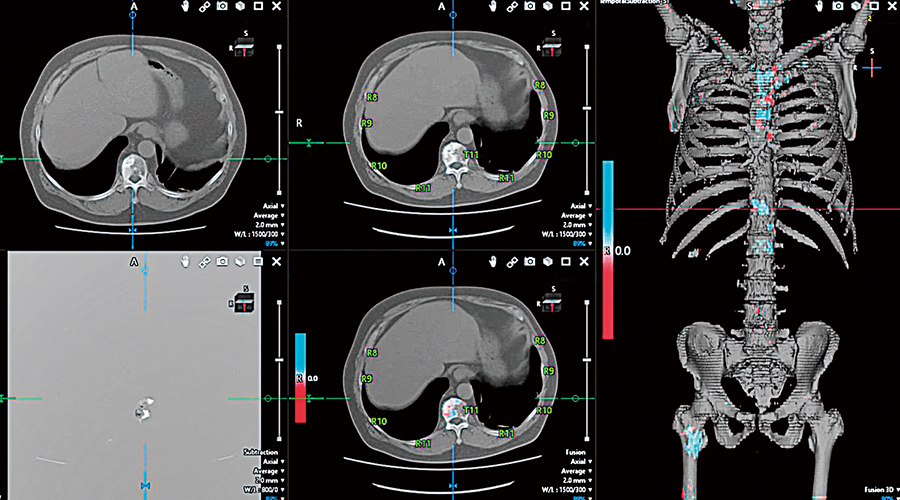

Recently, advances in medical equipment and the increase in examinations have led to longer image interpretation times and a greater burden on radiologists. Using a vast amount of image data from clinical practice and obtaining analysis results through deep learning,* Canon assists in image interpretation for cerebral stroke and bone metastases. With integrated time series display of patient diagnostic images, medication histories, and vital information including body temperature and blood pressure, Canon also focuses on digital transformation to reduce the burden on healthcare professionals.

Image interpretation software to support observation of changes to bone over time